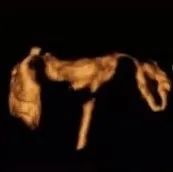

和平妇产医院子宫输卵管4D超声造影,是通过向子宫腔注入新型超声造影剂,利用声学造影剂显示造影效果,在美国GE-E10四维彩超监测下,360°立体动态成像,显示子宫情况、输卵管形态、输卵管积水、通畅情况、伞端是否与周围组织粘连,便于输卵管通畅性的评估和分析。通常做完造影后,休息两周后即可备孕。